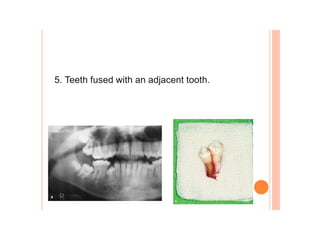

Dental caries, also known as tooth decay, is caused by certain types of acid-producing bacteria in the mouth that damage tooth structures when fermentable carbohydrates like sugar are present. It can lead to pain, tooth loss, infection, and in severe cases, death. While early signs may include white spots on teeth, untreated caries will form cavities. Risk factors include poor oral hygiene, frequent sugar consumption, dry mouth, and tobacco use. Treatment involves removing decay, restoring teeth, or extracting severely damaged teeth to prevent further destruction and infection. Preventive measures include proper brushing, flossing, limiting sugar intake, dental sealants, and fluoride therapy.